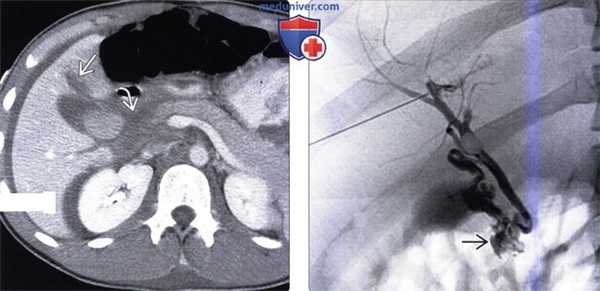

(Справа) На Т1 FS МР томограмме у этого же пациента визуализируется типичный желчный «цилиндр» с гиперинтенсивным сигналом в области бифуркации протока. Стриктуры желчных протоков и желчные «цилиндры», характерные для ишемической холангиопатии, могут возникать вследствие множественных поражений желчных протоков ишемического и иммунного характера.

(Слева) На корональной МРХПГ (МIP-реконструкция) у пациента с тромбозом печеночной артерии определяется диффузная деформация желчных протоков, с наличием хорошо заметных дефектов наполнения в просвете центральных протоков - изменения, сопоставимые с ишемической холангиопатией. Визуализируется дренажная трубка.

(Справа) На аксиальной Т1 ВИ МР томограмме у этого же пациента определяется диффузное расширение желчных протоков с наличием «цилиндров» с гиперинтенсивным сигналом на Т1 ВИ, вызывающих расширение желчных протоков. Также визуализируется дренаж установленный в расширенный желчный проток.